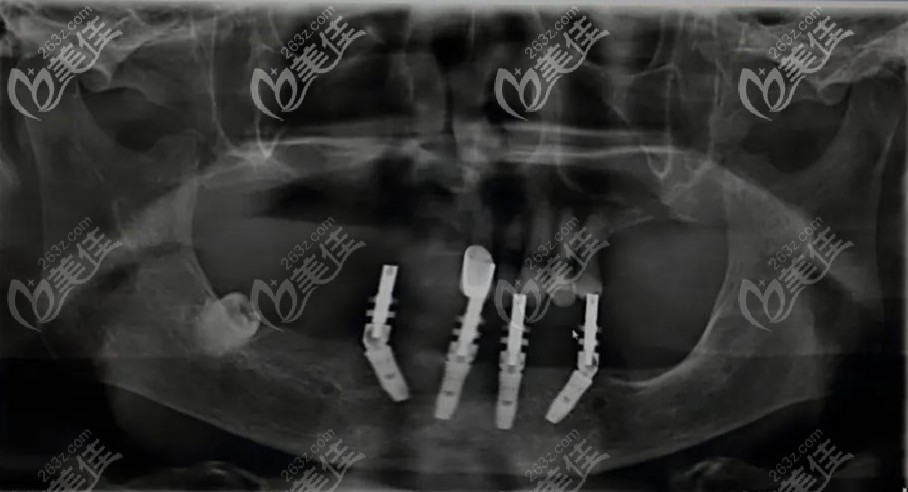

据悉,邓宏亮的微种植技术通过术前数字化扫描,精准获得缺牙者的口腔数据,以数据为基础重建口腔模型进行模拟种牙。

结合顾客的牙槽骨高度、密度、宽度,再按照自然牙的排列位置和咬合习惯进行设计。

手术时种植精度高达1微米,精准定位、准确植入、不需要翻瓣、恢复更快,平均8分钟就可以种好一颗牙。